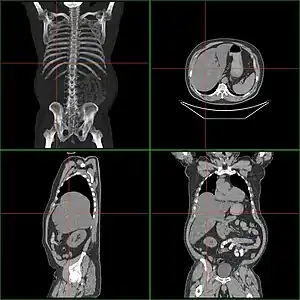

| Computerized tomography of affected person with hepatomegaly | |

-

Computed tomography finding of hepatomegaly. -

Computerized tomography (CT) can help to obtain accurate anatomical information, in individuals with hepatomegaly for the purpose of a complete diagnosis.[21]